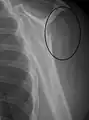

Multi-fragmented, or comminuted fracture of the proximal humerus with involvement of the greater tuberosity

Proximal humerus fracture